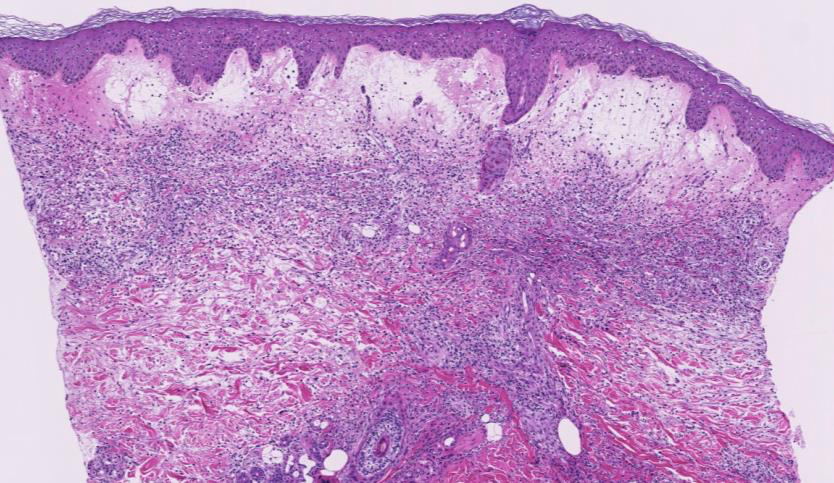

ALOPECIA AREATA